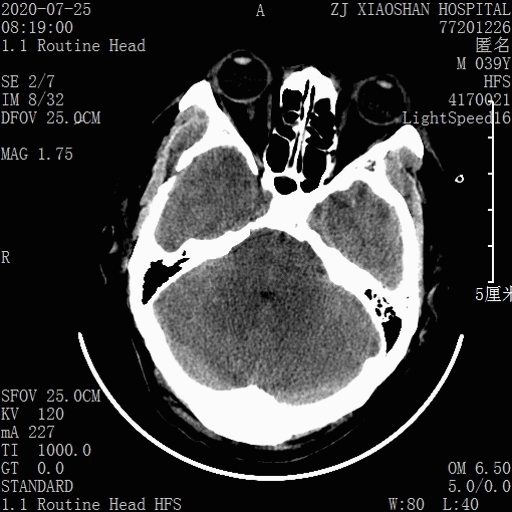

术后第一天CT: